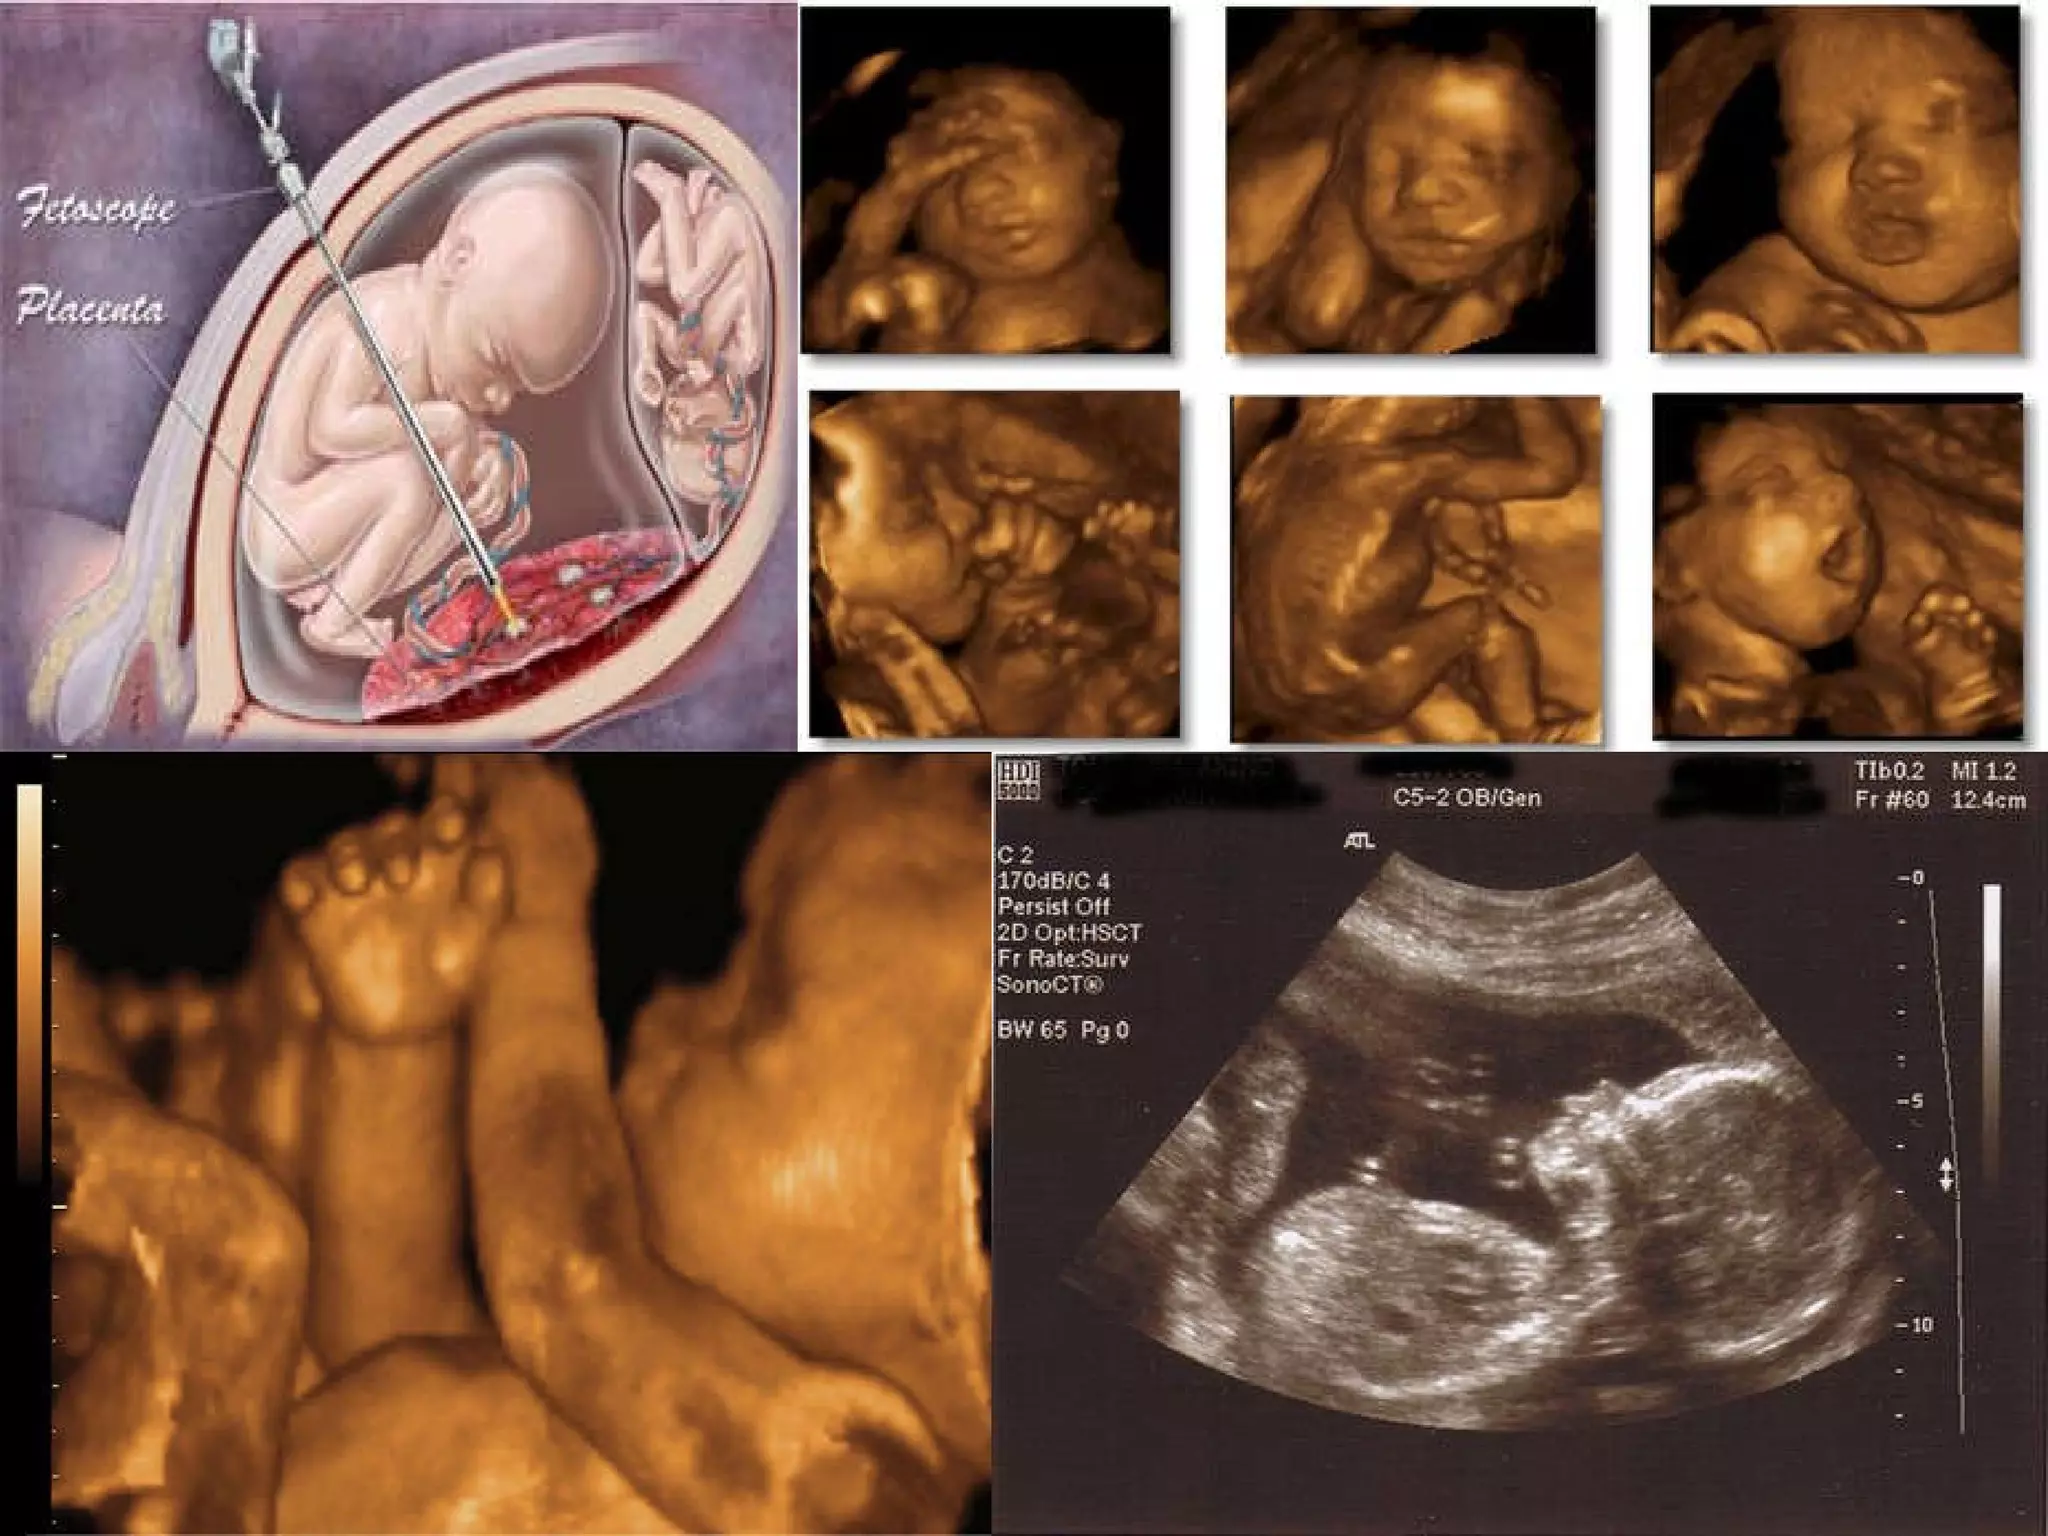

An ultrasound is generally performed for all pregnant women at 20 weeks of gestation. During this ultrasound, the doctor will confirm that the placenta is healthy and attached normally and that your baby is growing properly in the uterus. The baby's heartbeat and movement of its body, arms, and legs can also be seen on the ultrasound. The gender of the baby can usually be determined at 20 weeks.

Assessment  of the Fetal Well Being Fetoscopy Visualization of the fetus by inspection through fetoscope To confirm the intactness of the spinal column To obtain biopsy samples of the fetus To perform elemental surgery Can be performed as early as the 16 th  or 17 th  week

An ultrasound isgenerally performed for all pregnant women at 20 weeks of gestation. During this ultrasound, the doctor will confirm that the placenta is healthy and attached normally and that your baby is growing properly in the uterus. The baby's heartbeat and movement of its body, arms, and legs can also be seen on the ultrasound. The gender of the baby can usually be determined at 20 weeks.

Assessment ofthe Fetal Well Being Fetoscopy Visualization of the fetus by inspection through fetoscope To confirm the intactness of the spinal column To obtain biopsy samples of the fetus To perform elemental surgery Can be performed as early as the 16 th or 17 th week